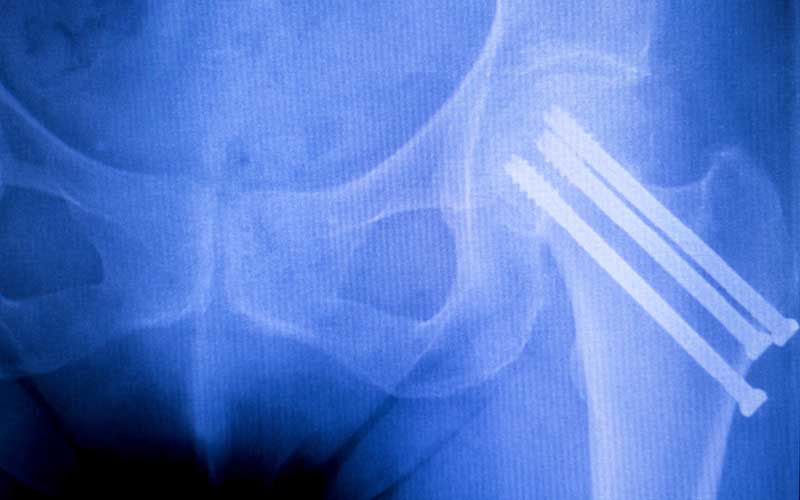

Since 2009, Our Implant Audit Services have focused on pre-payment, re-pricing and validating charges for implantable devices. We provide a multifaceted audit approach that combines implant industry experts experienced in selling to hospitals and surgeons.

Implant Audit Services